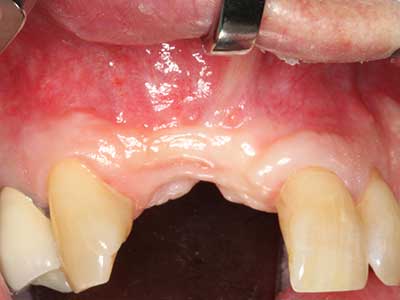

Маргиналните пародонтални заболявания са основната причина за екстракции в напреднала възраст. Тези болести се появяват главно от бактериална колонизация на гингивалния джоб, който причинява възпаление, последвано от загуба на периодонциума. Образуването на субгингивален биофилм и конкременти е значителен етилогичен фактор за маргинална костна атрофия, така, че тяхното отстраняване е важна част от лечението (Drisko 2014, Plessas 2014).

Първоначалната и хирургичната фаза на лечение са разграничени в лечението от периферен пародонтит. В допълнение към обучението по орална хигиена и мотивацията на пациентите, двете фази трябва да включват подходящо почистване на кореновата повърхност. В регенеративната настройка, отвореният достъп обикновено е за предпочитане. Кореновата повърхност може да бъде почистена с пиезохирургия чрез използването на специални накрайници с различни извивки за достигане на труднодостъпни зони, например фуркации. Интегрираното охлаждане в системата отмива прилепналите конкременти и бактерии навън от джоба. Специализираните системи като Piezomed включват приложение за обратна връзка за намаляване на аблацията на твърди дентални субстанции. Колкото по-голям е натискът върху пародонталния накрайник, толкова по-голяма е редукцията на количеството на аблация.